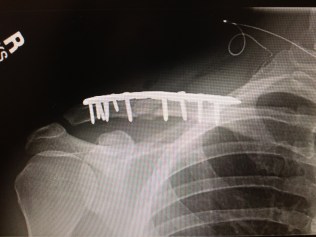

Mike fell off a bike in Aspen last Summer.

He hurt himself pretty bad.

In the months following my bike accident, I slowly graduated from physical therapy to running, weight lifting and yoga. But I had avoided getting back on a bicycle until I made it to the six-month mark, at which time, about 50% of people with titanium collar bones get their plates removed due to discomfort or complications.